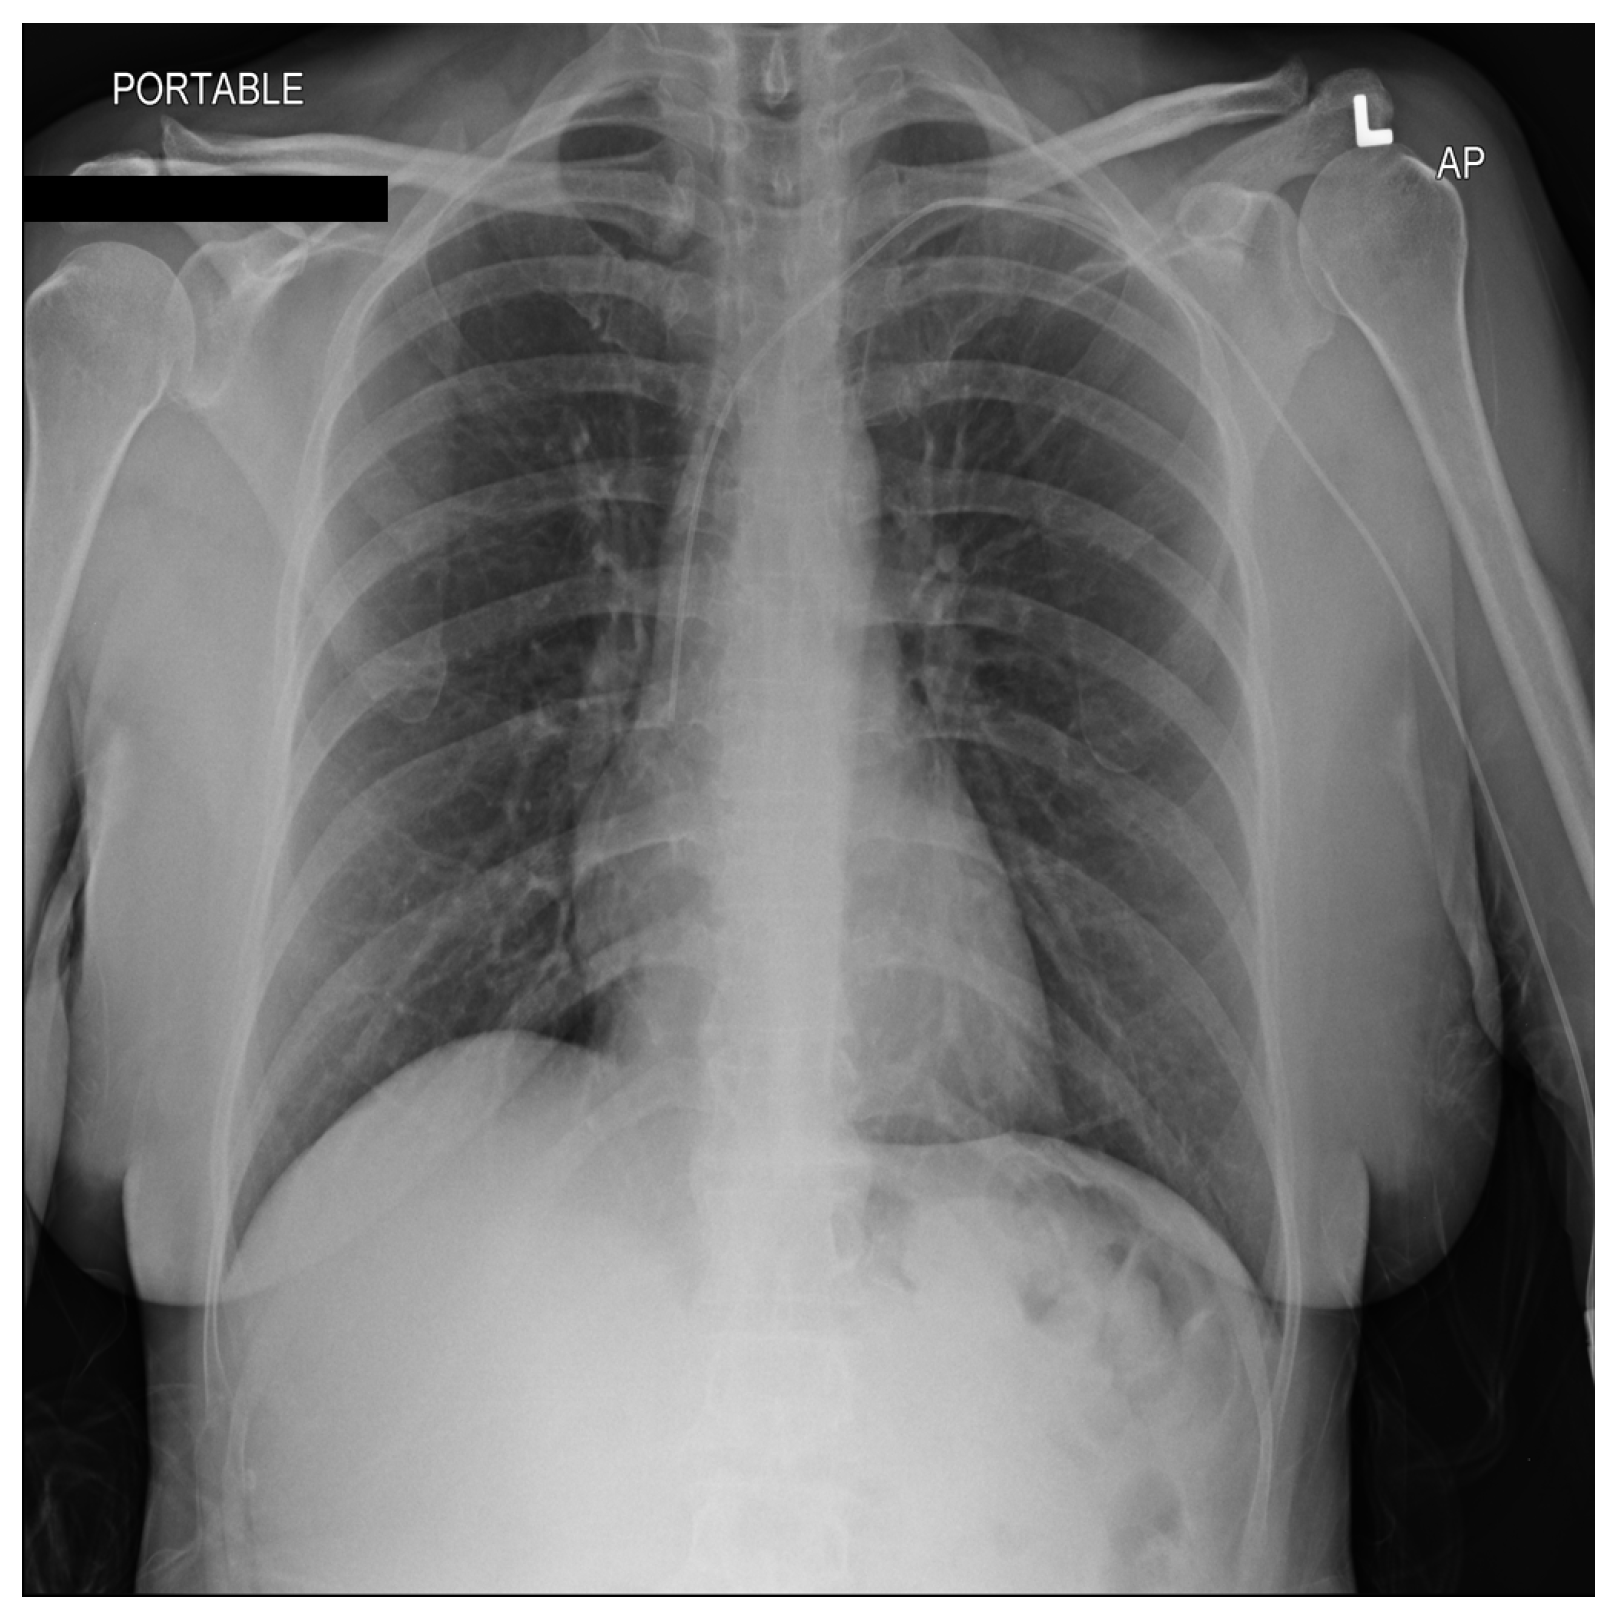

From a visual perspective, as illustrated in the comparison images above, both the RSCM as in Figure 1 and NIH as in Figure 2 datasets exhibit comparable quality in terms of resolution, clarity, and diagnostic relevance. This similarity ensures that image quality does not introduce any significant bias or variation.

Figure 2.

Sample image from the NIH dataset. L: Left.